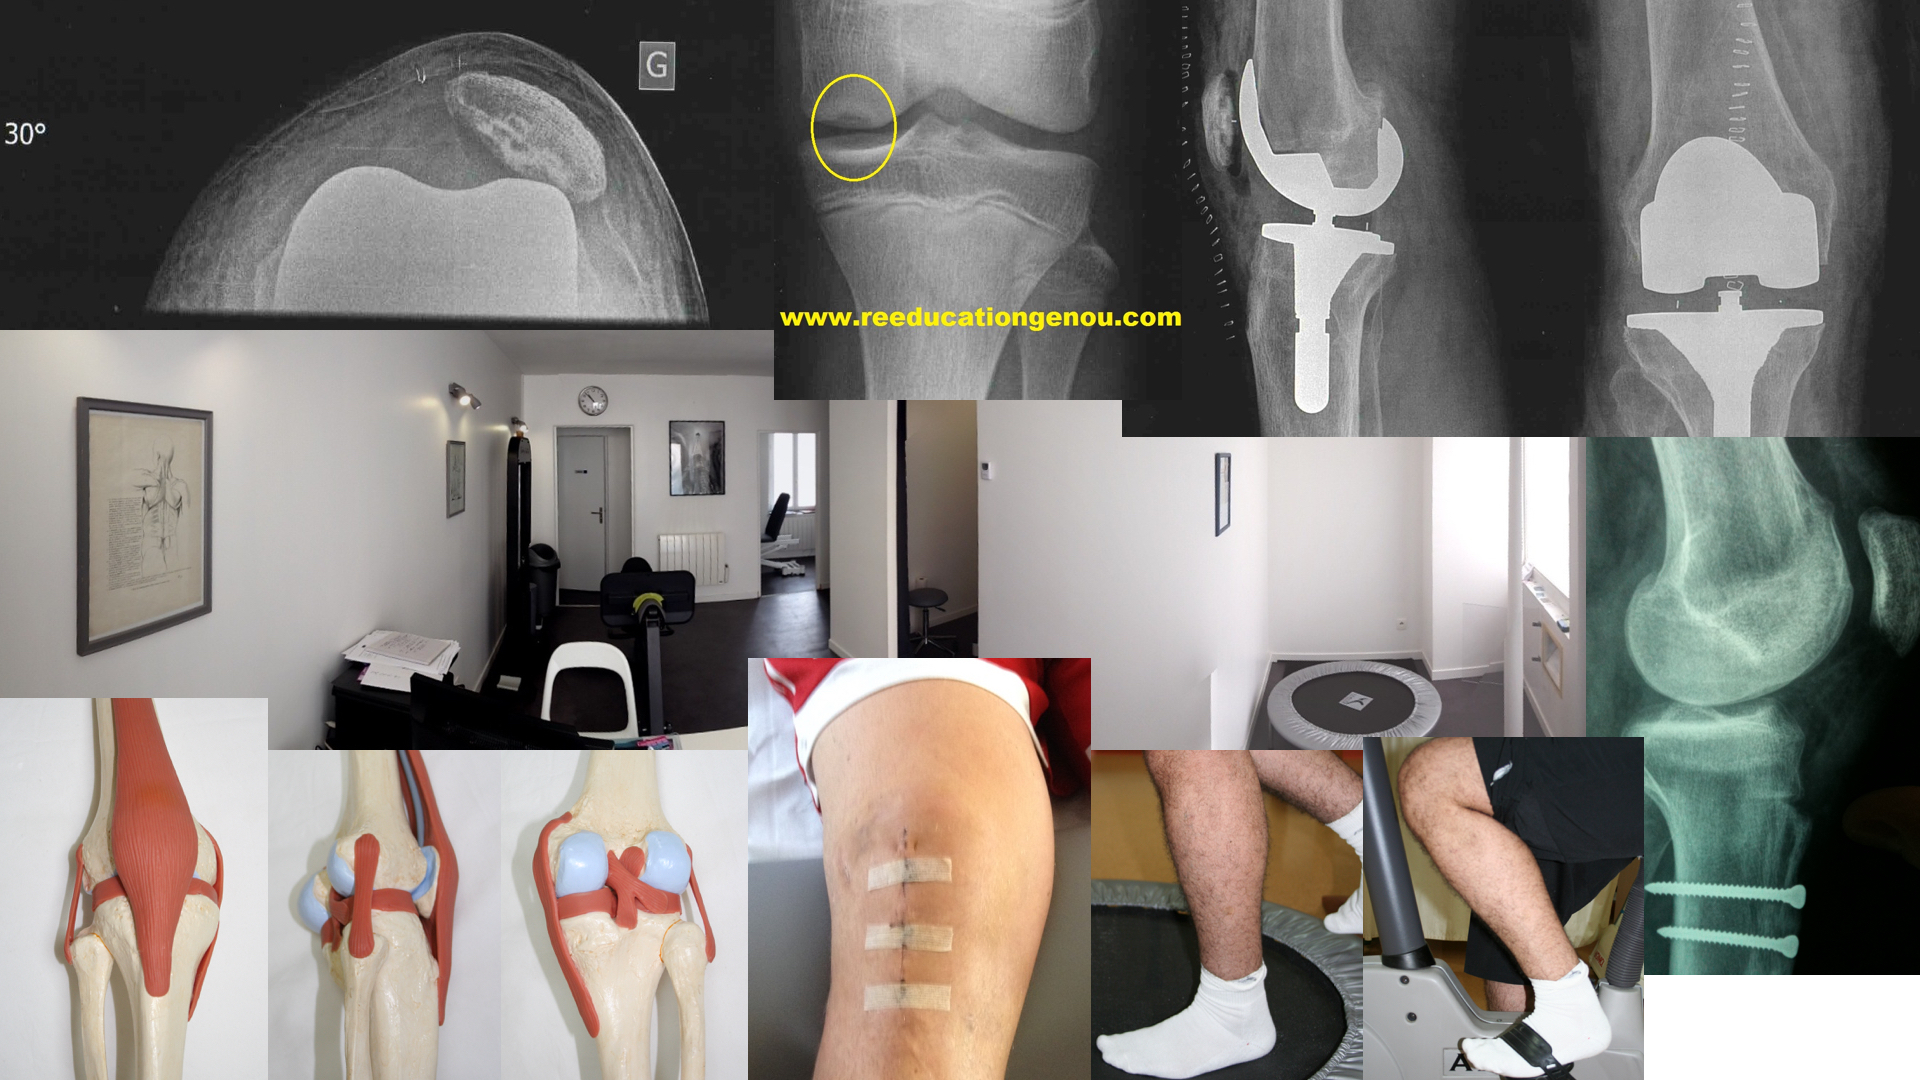

Rotule instable ou rotule luxée / après luxation

LA ROTULE INSTABLE (ou luxée ou opérée) / principes si opération du MPFL

La trochlée fémorale qui reçoit la rotule est peu creusée. Plus rarement elle peut être convexe (mesure radiologique de l'angle d'ouverture).  La rotule est alors très/trop mobile.

Pour faire simple, le couple trochlée et rotule si ils ne sont pas très anatomiquement bien constitués ont une tendance à se luxer en dehors, c'est la rotule dysplasique par insuffisance. Le ligament MPFL qui est le plan moyen de l'aileron médial (rétinaculum médial) est le seul rempart de la luxation quand e genou est quasi tendu or il est souvent lésé et déchiré dès la 1ere luxation...